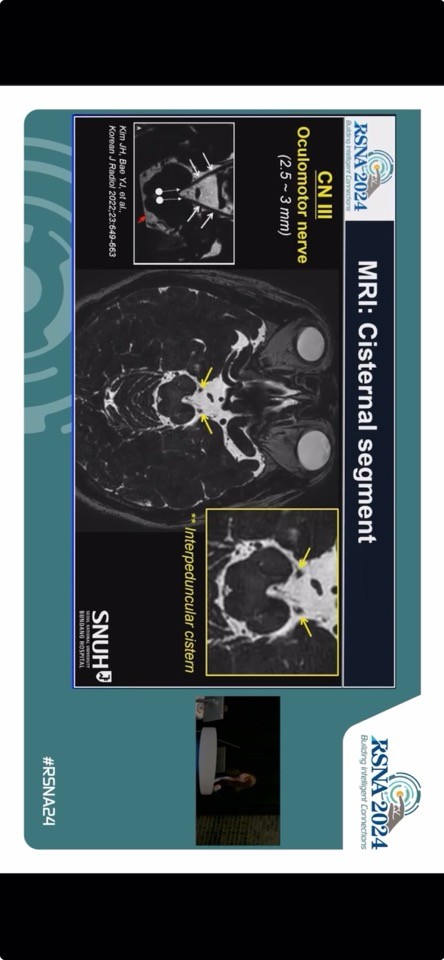

강연의 핵심은 복시의 원인질환 진단에 대한 첨단 MRI 영상 프로토콜이었다. 배 교수는 복시가 단순한 안구 증상을 넘어 중추신경계 병변의 중요한 신호가 될 수 있음을 강조하며, 고해상도 MRI 기법을 통해 뇌신경의 정확한 병변 위치와 원인을 규명하고 이에 따라 환자 치료 예후를 개선할 수 있음을 입증했다. 특히 단안 복시와 양안 복시를 감별하는 과정과 더불어 최신 기법의 고해상도 MRI를 활용한 제3, 4, 6번 뇌신경 (CN III, IV, VI)의 시각화가 임상 진단에 중요한 역할을 하는 점을 강조했다.

덧붙여 3D 고해상도 T2, Proton density, 조영증강 T1 강조 영상 등을 활용한 진단법과 최신 연구 결과를 공유하며 뇌간 병변, 신경근접합부 이상, 외안근 질환 등 다양한 임상 사례를 제시해 그 효용성을 보여주었다. 최근 국내 영상의학의 발전 덕분에 세계적으로 우수한 수준의 뇌신경 영상을 제시했다는 호평을 받았다.